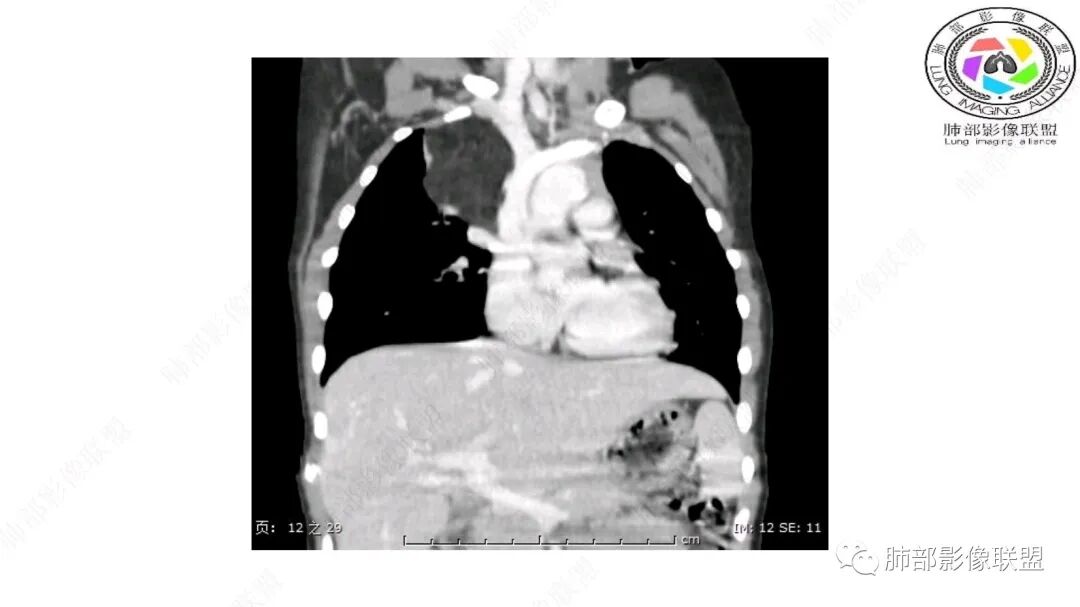

病灶属于交界区,主体位于肺内,占位效应明显,前方突入胸壁,胸腺受压变形,胸膜显示欠清楚;病灶包绕上叶肺动脉;似乎有体动脉供血。符合肺内的点:包绕上叶肺动脉分支;符合纵隔的点:前方似乎突入胸壁,与胸腺关系比较密切,但是与上腔静脉的关系提示病灶不支持纵隔来源,前纵隔的常规会将上腔静脉受压后移、外移,这是不符合的。

1.右上肺-纵隔交界区巨块影,主体位于右肺一侧,紧贴胸腺、头臂干、右锁骨下动脉、上腔静脉、奇静脉等,不能分离,但病灶整体边界清楚。注意上述相邻腔静脉等结构未见受压变形,纵隔亦未见明显向左推移,至少提示两点:

1)病灶相当柔软。

2)位于纵隔内或纵隔胸膜的可能性较小,因为受纵隔胸膜反作用力影响不明显。

2.肺动脉穿行也许是肺内来源最重要支持点!

CT扫描对脂肪类肿瘤常有独到价值。肿块孤立、边界清楚,未见周围浸润,较均匀脂肪样低密度,高度提示为良性!

发生于成人为脂肪瘤表现,婴幼儿自然会想到脂肪母细胞瘤。两者生物学行为并无本质区别。